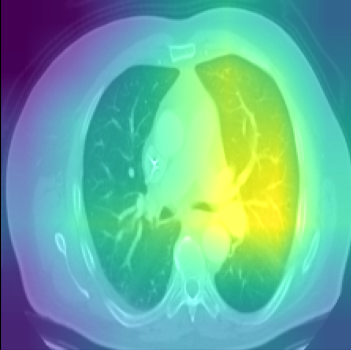

Class activation heat-map development

The final step involves the generation of feature visualisation heat-maps, elucidating the decision-making process of the trained model, and assessing its reliability. Feature visualisation is valuable for uncovering and understanding the learnt features within DL models. Zhou et al. (2016) introduced the Class Activation Mapping (CAM) method, which incorporates a global average pooling layer into a standard CNN. This innovation facilitated the identification of critical feature contributions linked to CNN’s specific predictions, shedding light on the rationale behind the model’s decisions. Furthermore, Selvaraju et al. (2017) introduced Gradient Weighted Class Activation Mapping (Grad-CAM), using gradients from the network’s final convolutional layer to generate a coarse localisation map. This map highlights influential regions within an image that contribute to the prediction of specific concepts or classes. In our study, we embraced the Grad-CAM technique on the model’s final layer to generate class-specific heat-maps. The objective is to unveil evidence of how the models arrive at predictions, with the heat-maps delineating regions of significance in the model’s prediction rationale.

Comparison using XAI techniques